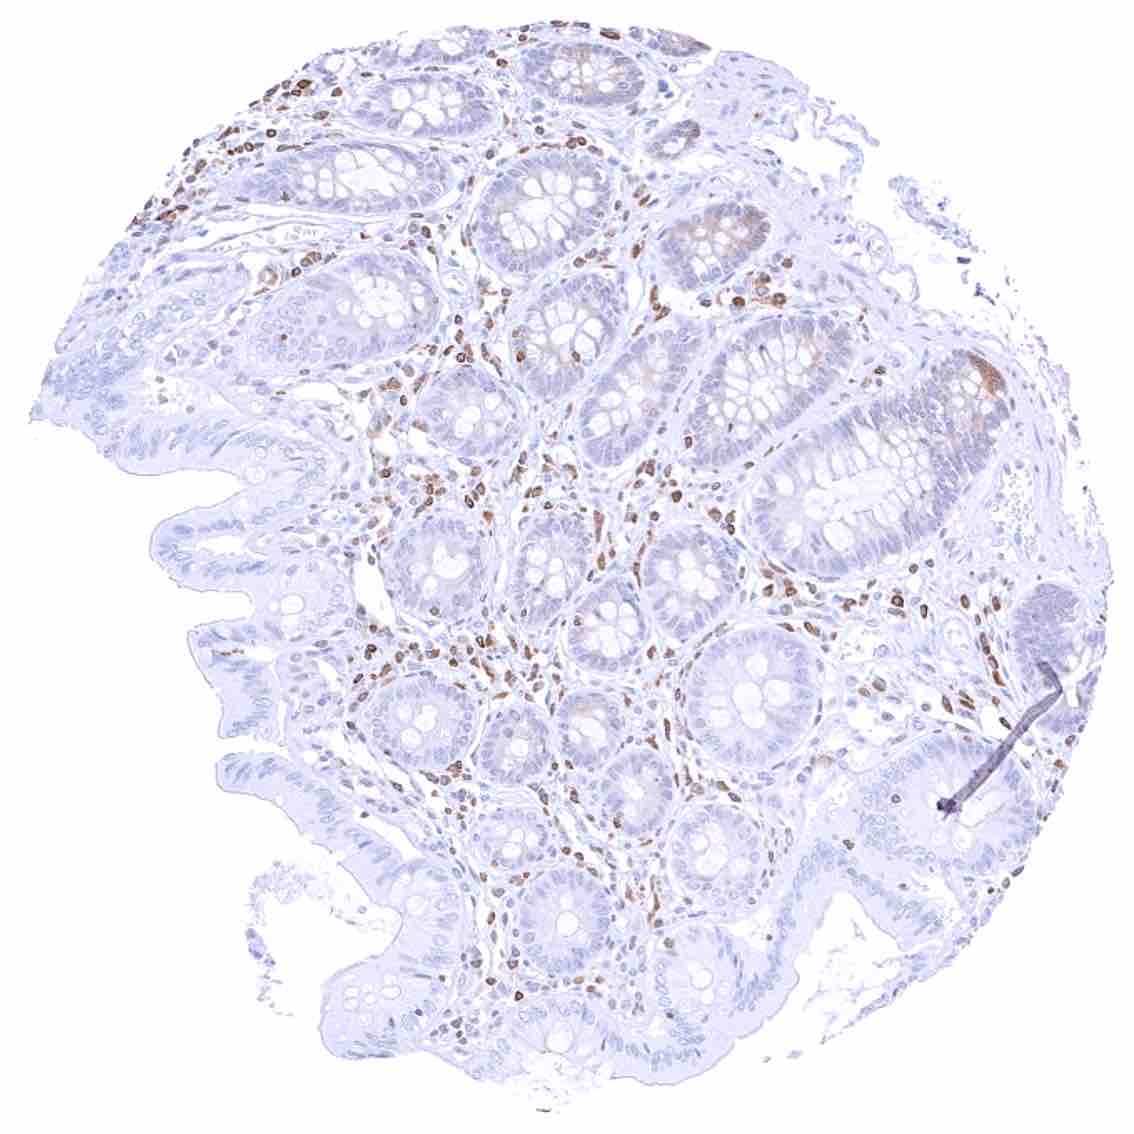

Duodenum, mucosa – Cytoplasmic bcl-2 staining is largely limited to lymphocytes. The epithelium is mostly negative, but a weak staining occurs in some crypt cells.